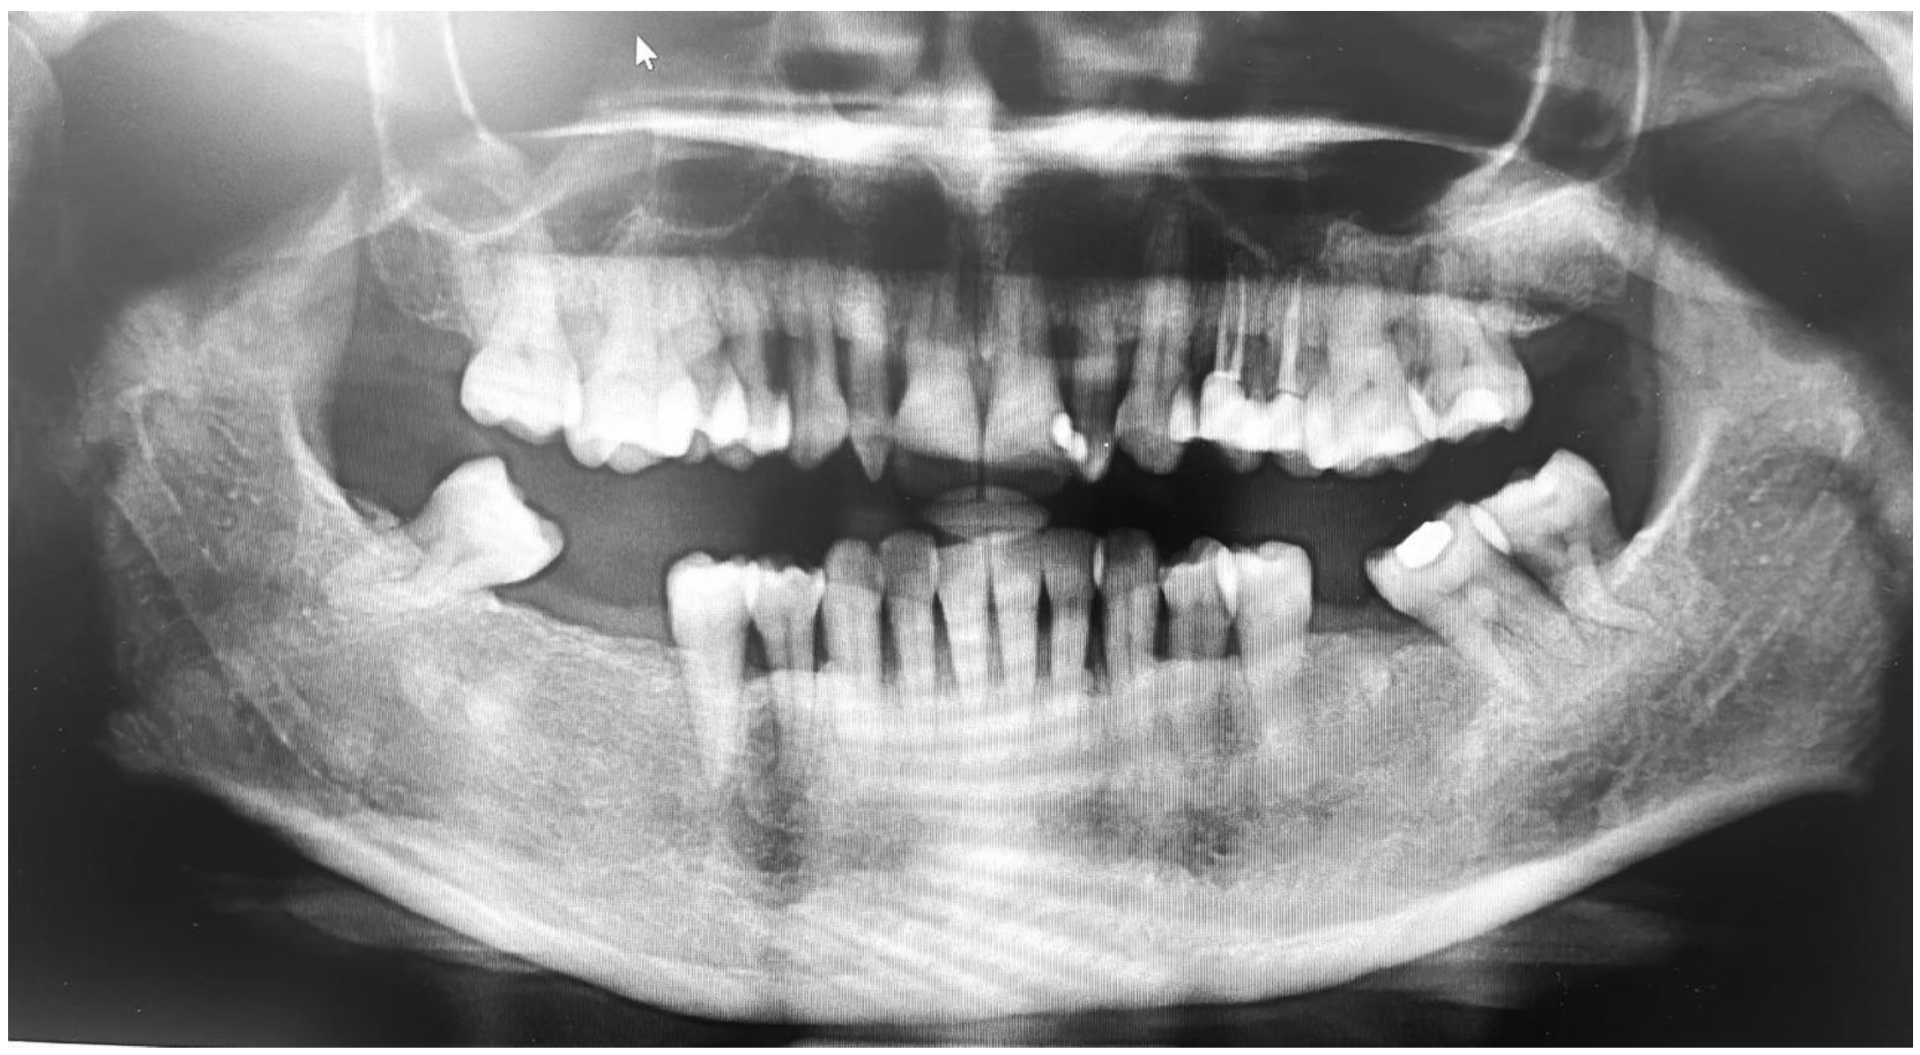

Extraoral examinations were within normal limits, focusing on facial symmetry, temporomandibular joint (TMJ), and potential trigger points of trigeminal neuralgia (TN). Upon intraoral examination, the patient had localized gingival inflammation in the upper and lower anterior areas, with punched-out papillae similar to necrotizing uncreative gingivitis (NUG). There was gingival recession of 2–7 mm, along with visible plaque and calculus in the same area and associated halitosis (Figure 3A–D). However, the pocket depth was not recorded due to severe pain upon touch, with a score of 9 out of 10 measured on the visual analog scale (VAS). Active dental caries at #16, 17 and previous restorations at teeth #24, 25, 37 were also observed (Figure 4).

Figure 4. Orthopantomogram showing generalized horizontal bone loss, multiple missing teeth, and restorations.